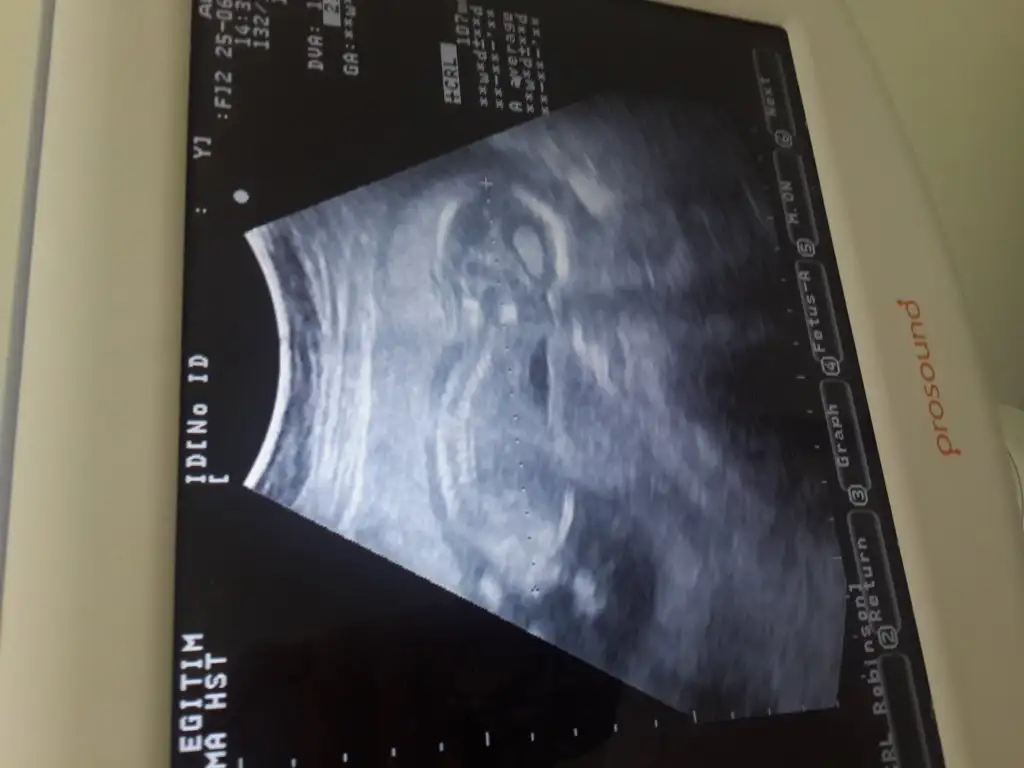

Ultrasonda hersey normaldi. 1.8 di ense kalinligi. Yas riskimde yok ama digeri 1/186 ciktiense kalınlığ kaç çıkmıştı yaş riskin mi yoksa kombine risk mi yüksek çıktı ..benim kombine 2190 çıkmıştı doktor iyi demişti

canım kombine risk mi 186 çıktıUltrasonda hersey normaldi. 1.8 di ense kalinligi. Yas riskimde yok ama digeri 1/186 cikti